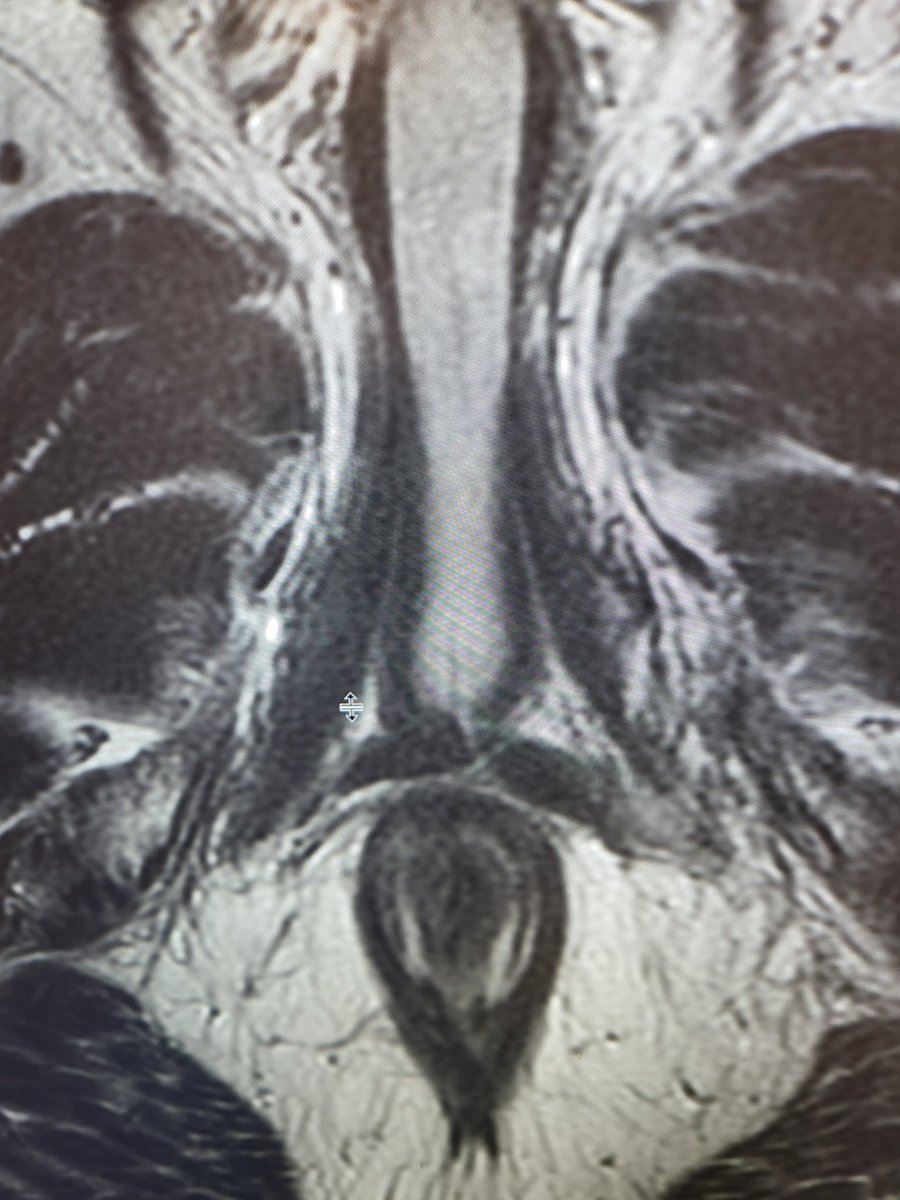

Have you ever seen transverse perineal muscles this thick? Ques : Wht are the functions of transverse perineal muscles? Answer in comments. SAR Prostate DFP Yale Radiology Residents